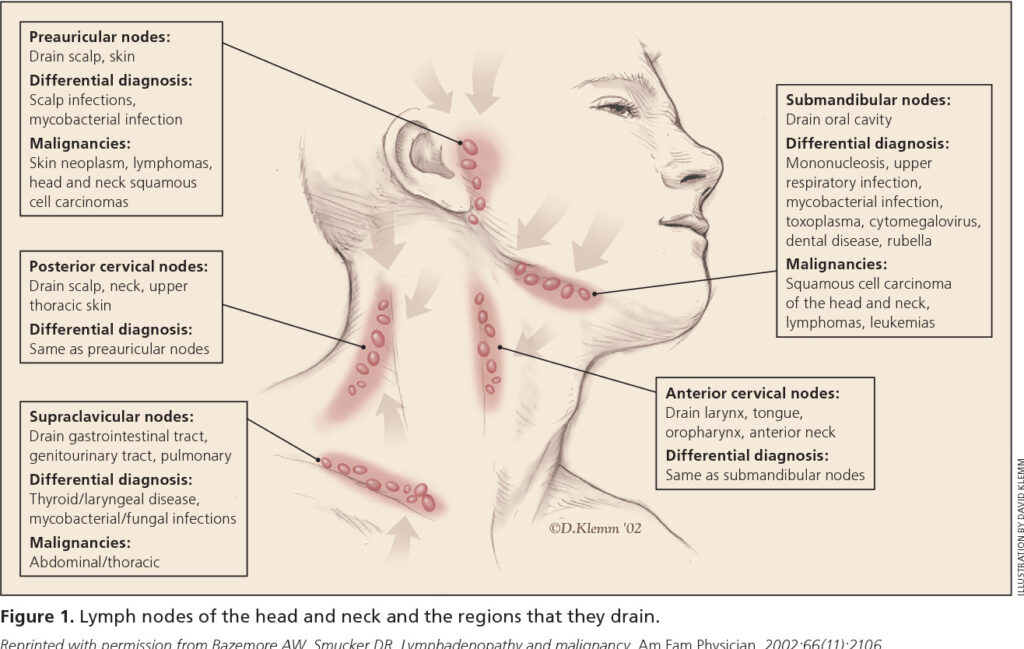

Nổi hạch

Đối với vị trí hạch nổi ở vùng cổ, bạn có thể dễ dàng phát hiện bằng cách sờ tay vào vị trí sưng đau. Người có nguy cơ mắc bệnh ung thư họng sẽ thường xuyên sổ mũi hoặc đau rát tập trung một bên cổ họng và không có tác dụng khi uống thuốc.

Nếu có dấu hiệu nổi hạch và cảm thấy đau kéo dài, bạn hãy đi thăm khám ngay để kịp thời phát hiện và điều trị kịp thời nhé.

Với các triệu chứng nhẹ, bác sĩ sẽ thăm khám từ ngoài vào trong bằng cách quan sát cổ, kiểm tra các hạch và quan sát bên trong lưỡi hay vòm họng.